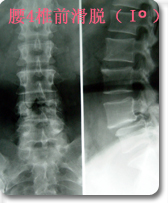

后路内窥镜下(XTube)经单侧神经孔腰椎体间融合,椎弓根螺钉复位内固定术(TLIF)

采用后路内窥镜下(XTube)经单侧神经孔腰椎体间融合,椎弓根螺钉复位内固定术,以治疗极外侧腰椎间盘突出(神经孔型)伴腰椎不稳。 优点:通过单侧经神经孔入路途径达到椎间隙,从而达到椎间减压和植骨融合目的。该手术途径单侧入路,显露清楚,不需过度牵拉神经。为外科医生提供了一个能显著减少PLIF手术的很多风险和限制的融合方式。本手术将内窥镜(XTube)与TILIF手术的优点集于一身达到更小的创伤更好的手术效果。